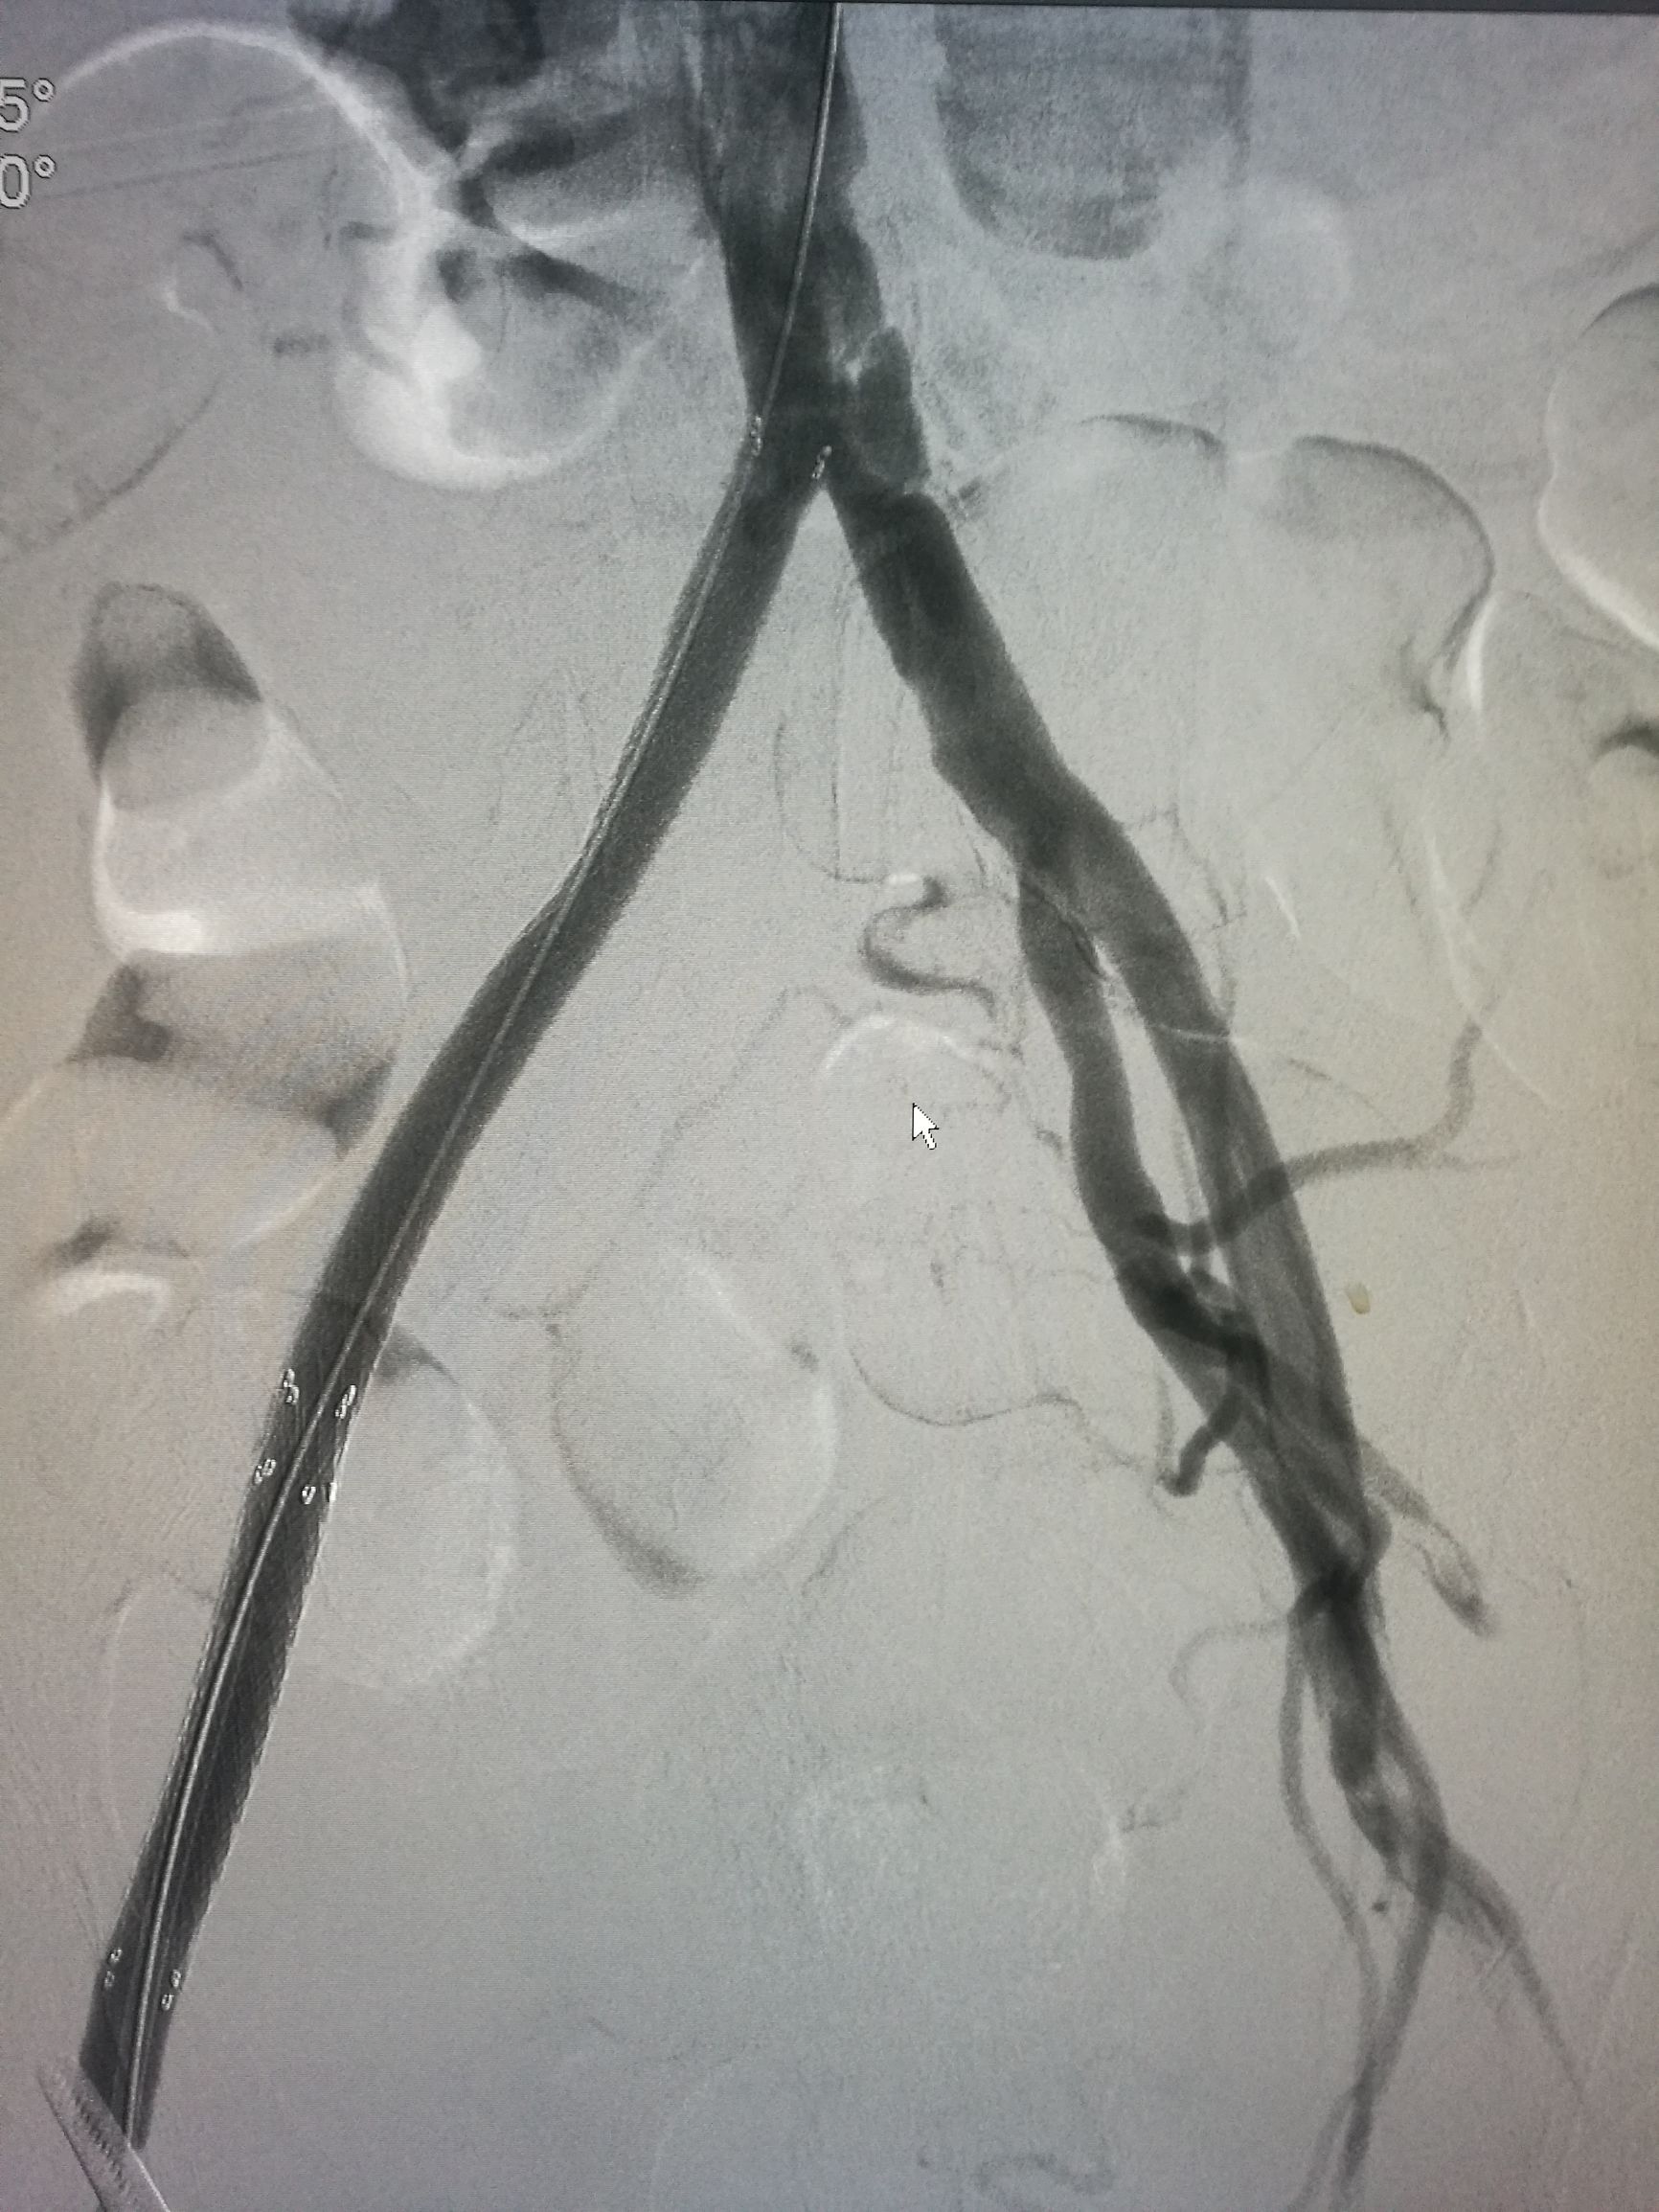

患者平卧位,常规消毒铺单,局麻下切开显露右侧股总动脉和股深动脉、股浅动脉。全身肝素化后,切开股动脉,对股浅动脉取栓后远侧回血好,对股深动脉反复取栓后出现汹涌回血。近端取栓后用导丝导管通过闭塞段到达腹主动脉下段,造影证实在真腔,用5*80mm球囊扩张后造影,髂动脉内有部分充盈缺损。植入巴德Fluency8*100和8*60覆膜支架后用7*60球囊扩张,造影管腔光滑(如图)。缝合动脉切口,关闭伤口,术毕。

术后右侧胫后动脉可以触及清晰搏动。